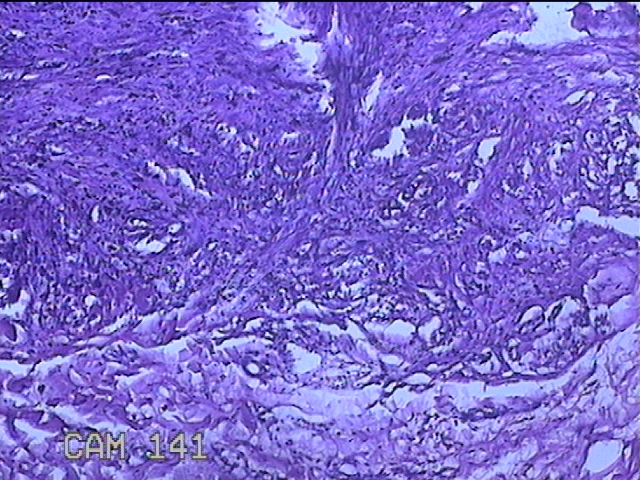

左侧臀部结节

性别

男

年龄

40岁

临床诊断

皮下结节

一般病史

发现左侧臀部结节1年余。

标本名称

大体所见

灰白粉红色组织1.3x0.8x0.3cm一块,表面带梭形皮肤1.3x0.8cm,皮下见结节1.3x1x0.7cm一个,切开结节呈实性,切面灰白粉红色,质软。

图1